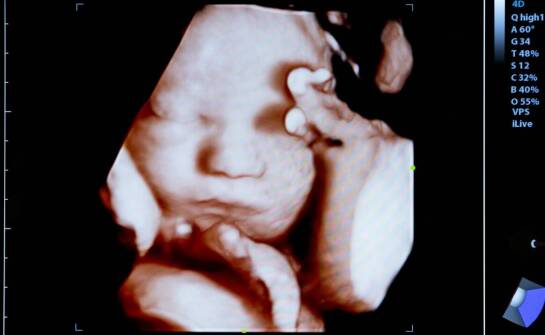

USG główki noworodka – przebieg badania i najważniejsze korzyści diagnostyczne

USG główki noworodka (USG przezciemiączkowe) pozwala szybko ocenić struktury mózgowia u niemowląt bez promieniowania i bez bólu. Badanie trwa zwykle 15–20 minut, nie wymaga specjalnego przygotowania i może być powtarzane. Największą wartością jest wczesne wykrycie nieprawidłowości, takich jak krwawi